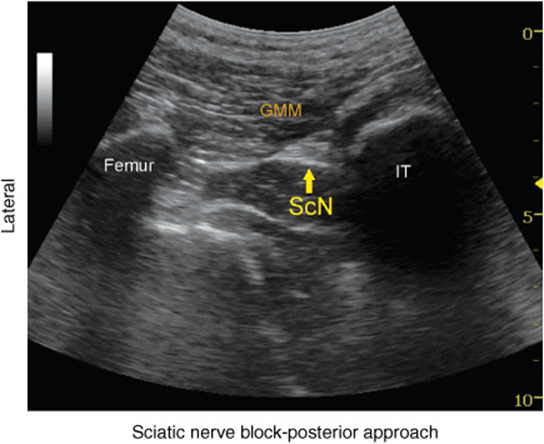

At this transgluteal level, the sciatic nerve is visualized in the short axis between the two hyperechoic bony prominences of the ischial tuberosity and the greater trochanter of the femur (Figure 39.2-1 and 39.2-2). The gluteus maximus muscle is seen as the most superficial muscular layer bridging the two osseous structures, typically several centimeters thick. The sciatic nerve is located immediately deep to the gluteus muscles, superficial to the quadratus femoris muscle. Often, it is slightly closer to the ischial tuberosity (medial) aspect than the greater trochanter (lateral). At this location in the thigh, it is seen as an oval or roughly triangular hyperechoic structure. At the subgluteal level, however, the sciatic nerve is positioned deep to the long head of the biceps muscle and the posterior surface of the adductor magnus.

FIGURE 39.2-2. An ultrasound image demonstrating the sonoanatomy of the sciatic nerve (ScN). The ScN often assumes an ovoid or triangular shape and it is positioned underneath the gluteus muscle (GMM) between the ischium tuberosity (IT) and femur.